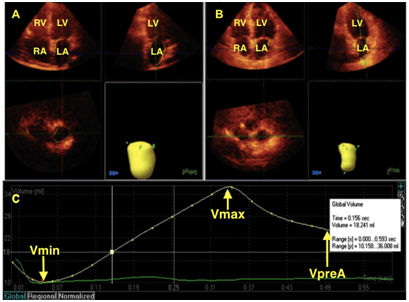

Figure 1 An example of left atrial volume quantification by real time three-dimensional echocardiography (RT3DE). Real time three-dimensional echocardiography recordings of max left atrial volume. (A) and min left atrial volume. (B) and time-volume curve. (C) indicating maximum and minimum left atrial volumes and before left atrial contraction volume. Vmax, maximum left atrial volume; Vmin, minimum left atrial volume; Vpre A, left atrial volume before atrial contraction

The importance of the LA in cardiovascular performance has long been acknowledged. The LA plays a pivotal role in stroke volume by modulating left ventricular (LV) filling with its reservoir, conduit, and contractile functions (Figure 1).1 The LA acts as a volume sensor of the diastolic burden, and communicates with the neurohormonal systems via the secretion of atrial natriuretic peptides.2 There is notable interplay between LA and LV function, such that events during each phase of “LA phasic function” are affected by factors from both the LA and LV.